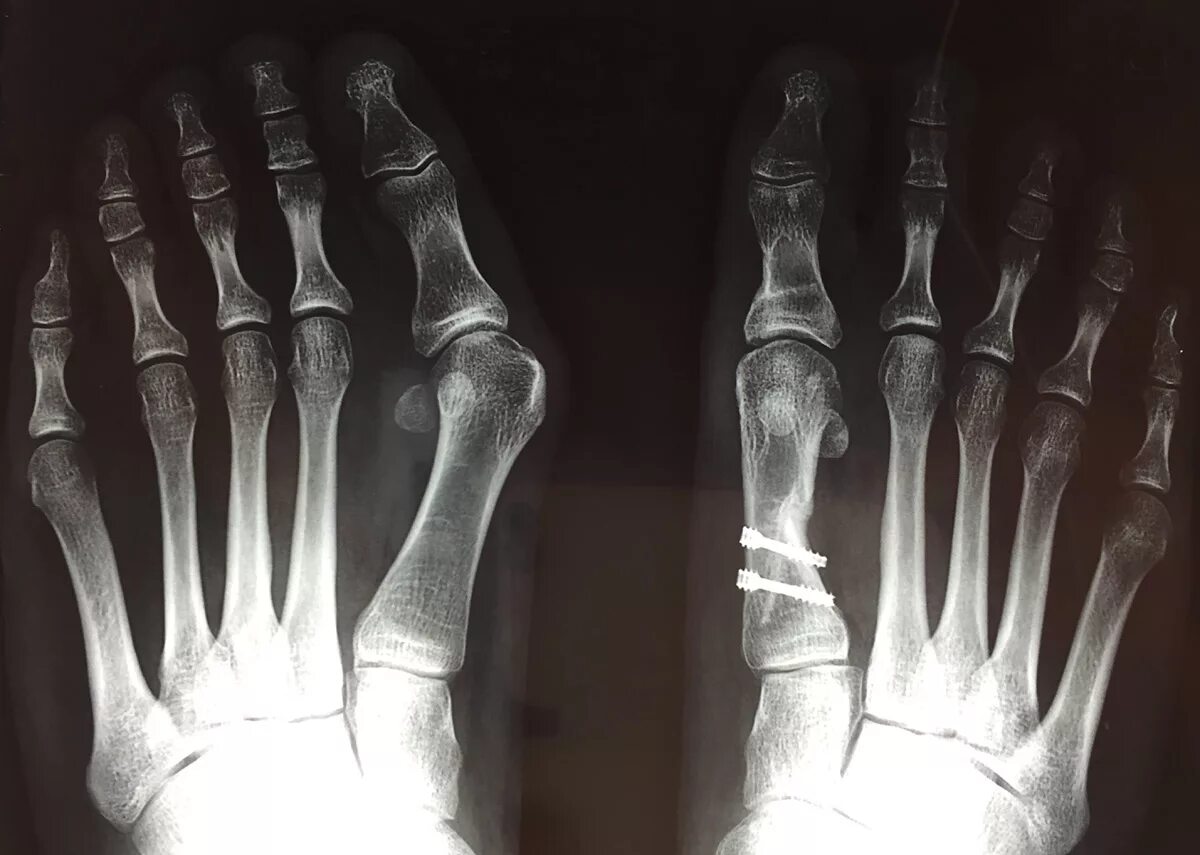

Степени вальгусной деформации 1 пальца стопы